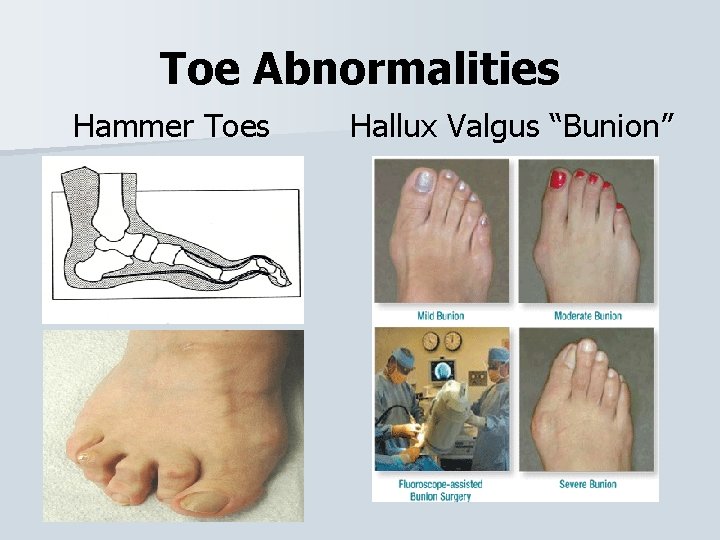

Toe Abnormalities n Hallux Valgus - Bunion n Hammer Toes – deformity at the PIP n Mallet Toe – deformity of the DIP n Claw Toe – deformity of the IP and DIP.

Toe Abnormalities Hammer Toes Hallux Valgus “Bunion”